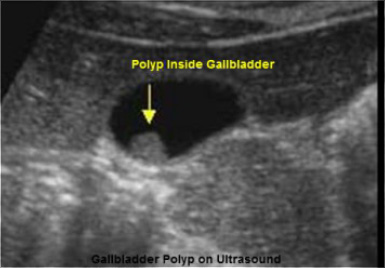

Οι πολύποδες της χοληδόχου κύστεως είναι ένα σχετικά συχνό εύρημα, περίπου στο 1-5% του ενήλικου, κυρίως, ανδρικού πληθυσμού και συνήθως ανακαλύπτονται τυχαία στον έλεγχο με υπερήχους σε περιπτώσεις διερεύνησης κλινικής συμπτωματολογίας του ανώτερου πεπτικού σωλήνα ή σε διερεύνηση παθήσεων του ήπατος και των χοληφόρων (π.χ. χολολιθίαση).(Εικόνα Β)

Εικόνα Β (υπερηχογράφημα)

Η διάγνωση της νόσου γίνεται με το υπερηχογράφημα άνω κοιλίας. Η διενέργεια άλλης απεικονιστικής εξετάσεως (π.χ. αξονικής ή μαγνητικής τομογραφίας) έχει επικουρικό χαρακτήρα.